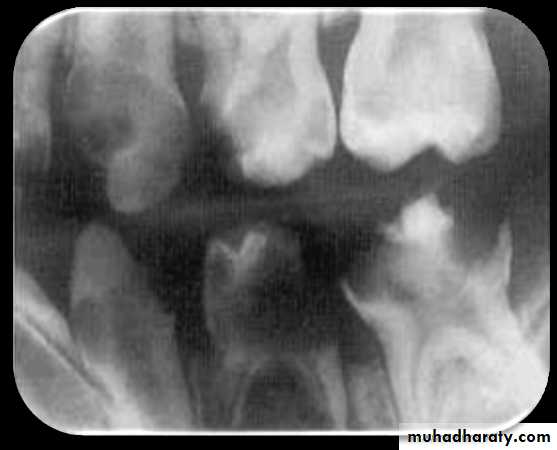

Rampant Caries

Advanced and severe caries that affects numerous teeth, rampant caries is seen in children with poor dietary habits or in adults with a decreased salivary flow.Radiolucent Cervical Burn-Out